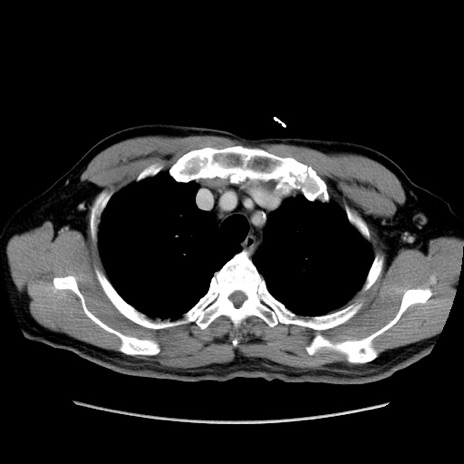

症例34(横断像)

【症例】60歳代 男性

【既往歴】高血圧

【データ】WBC 15500、CRP 測定なし